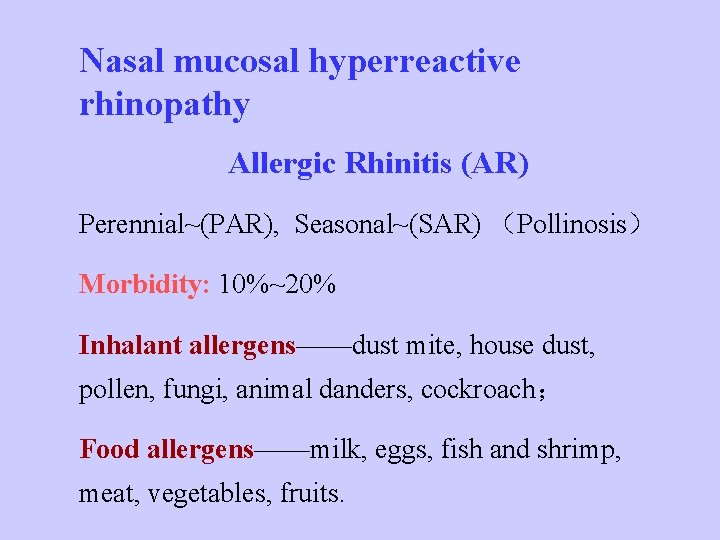

Nasal mucosal hyperreactive rhinopathy Allergic Rhinitis (AR) Perennial~(PAR), Seasonal~(SAR) (Pollinosis) Morbidity: 10%~20% Inhalant allergens——dust mite, house dust, pollen, fungi, animal danders, cockroach; Food allergens——milk, eggs, fish and shrimp, meat, vegetables, fruits.